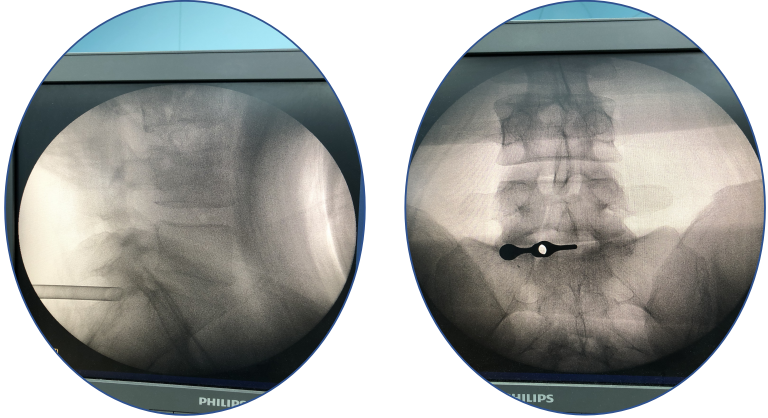

术前X线片

术中透视